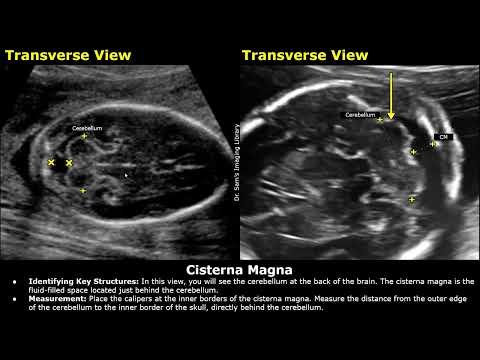

Как измерить большую цистерну плода на УЗИ | Сканирование аномалий головного мозга плода | Акушер...

Измерения плода, советы и рекомендации